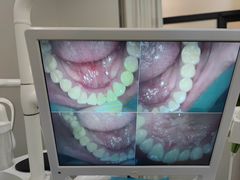

• 牙博士口腔品牌连锁(杨浦店)

• -牙博士口腔品牌连锁(杨浦店)